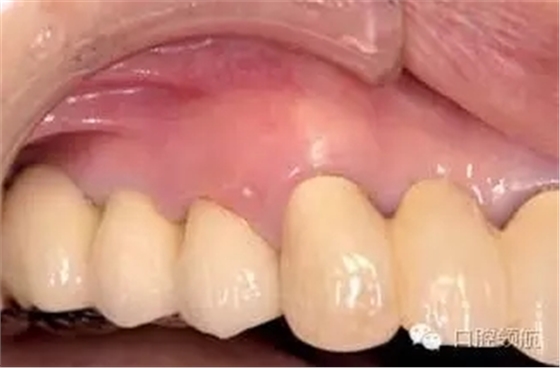

患者因?yàn)椋ㄗ笊系?顆牙) 種植體周?chē)つげ贿m為主訴來(lái)院。(圖1),2年前接受種植治療,每4個(gè)月檢查復(fù)診,但近幾周因身體的不適沒(méi)能堅(jiān)持做好清潔,臨床探診有出血,X線檢查后,沒(méi)有發(fā)現(xiàn)骨吸收現(xiàn)象(圖2)。

圖1 (左上第4顆牙) 種植體周?chē)つび胁贿m感,來(lái)院就診。